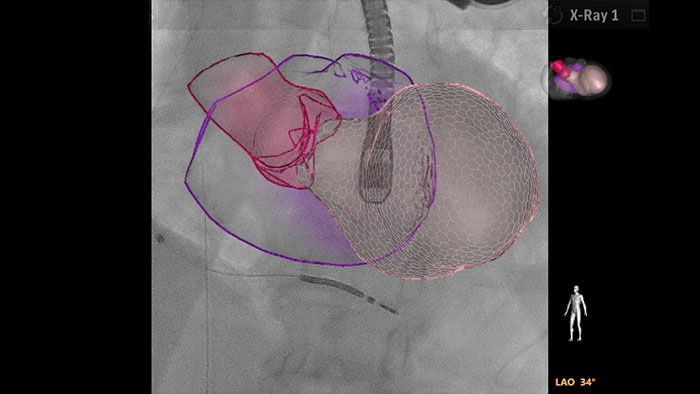

EchoNavigator reorienta y combina la información de ecografía y rayos X en una sola visualización aumentada para guiar y evaluar la relación dispositivo-tejido. Para la TAVR, EchoNavigator permite eliminar el contraste yodado para los pacientes con una función renal gravemente comprometida: